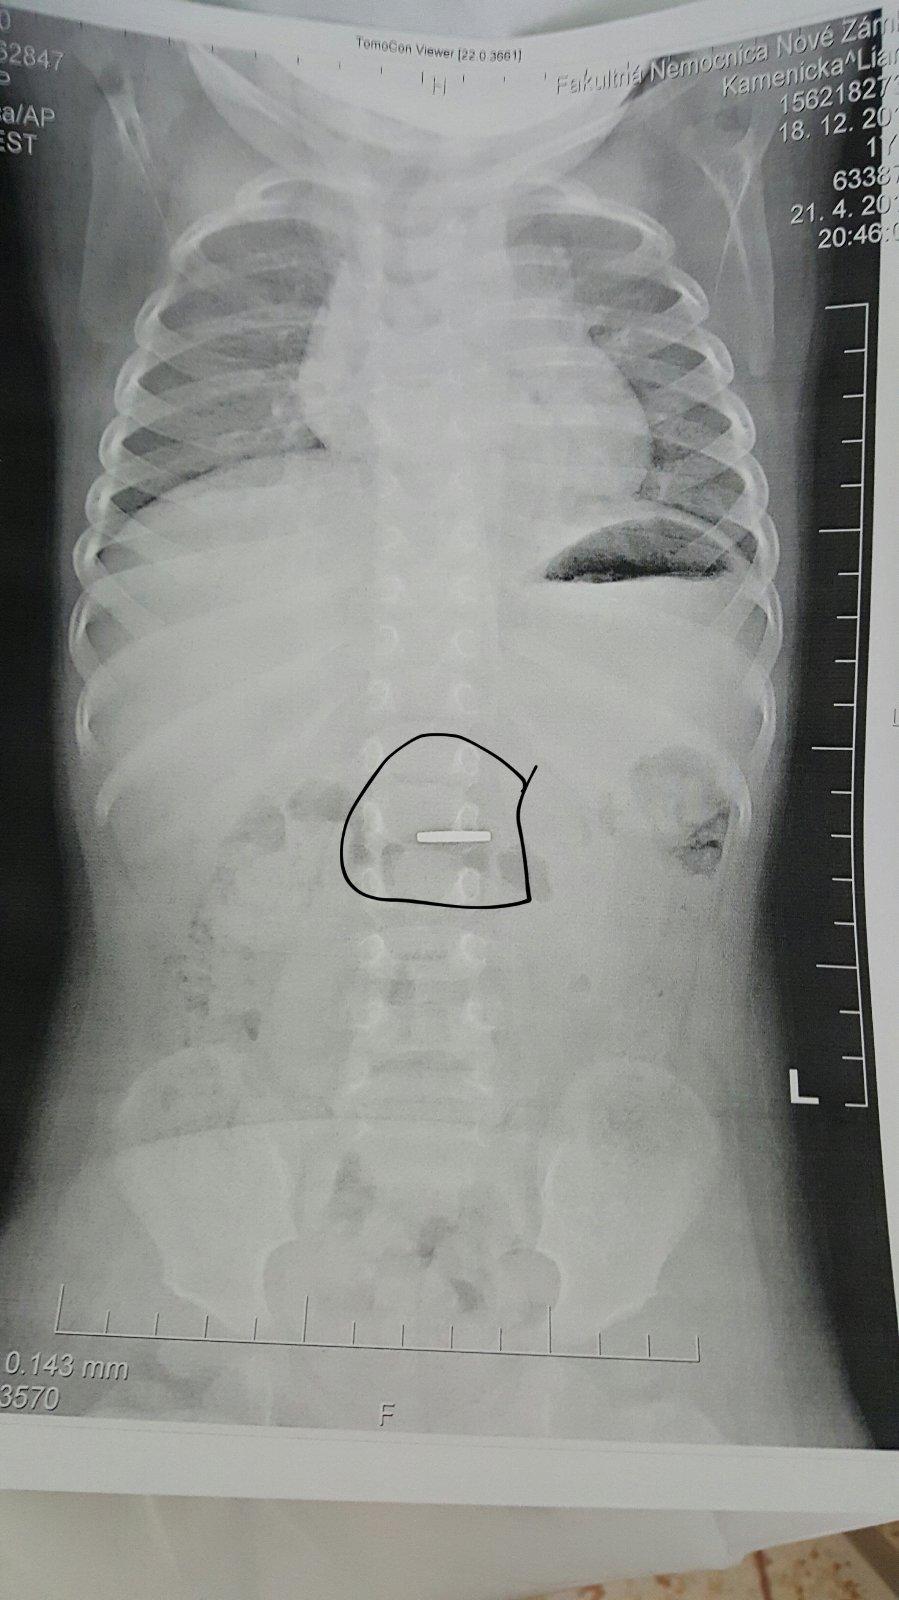

Ahoj, som pracovala v nemocnici a mávali sme deti, čo prehltli všeličo, mince najčastejšie....ono to vyjde samo? robili Vám Rtg brucha? Tam to pekne vidno, kde sa minca nachádza

Babyyy pomoooc sme v nemocnici moja mala zjedla dvojcentovku budeme tym kym to vykaka ale stalo sa vam niektorej nieco take? Mam strasne nervy nechcela to vyplut hodila hlavu dozadu a hned ju aj prehltla 😣